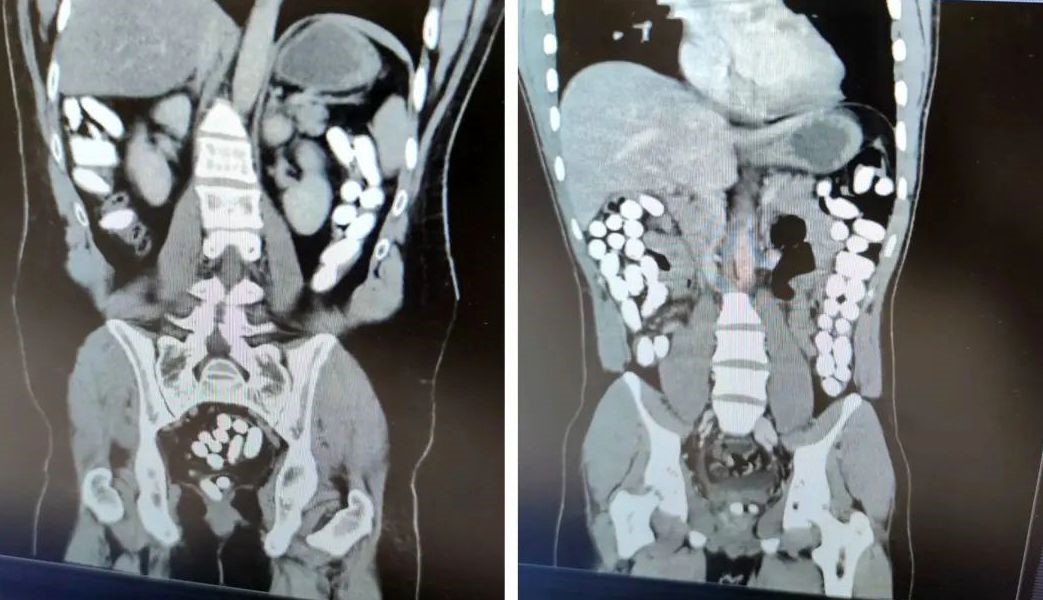

UYUŞTURUCU MADDELER TOMOGRAFİ ÇEKİMİNDE ORTAYA ÇIKTI

İl Emniyet Müdürlüğü Narkotik Suçlarla Mücadele Şube Müdürlüğü ile Kaçakçılık ve Organize Suçlarla Mücadele Şube Müdürlüğü ekiplerince yapılan çalışmada; Uygulama noktasında durdurulan yolcu otobüsünde yolcu olarak bulunan İran uyruklu A.G. (25) ve E.P. (21) İsimli şahıslara alınan karara istinaden yapılan tomografi çekiminde mide ve bağırsak kısmında uyuşturucu olabileceğini değerlendirilen çokça yabancı cismin olduğu görüldü. Yapılan tetkikler neticesinde A.G. (25) isimli şahıstan 100 parça halinde 847,64 gr gelen Afyon Sakızı, E.P. (21) isimli şahıstan 142 parça halinde 1071,80 gr gelen Afyon Sakızı ele geçirildi.